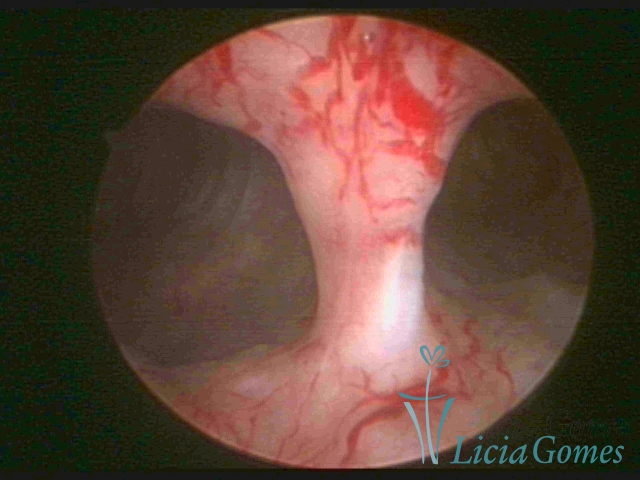

Bicornuate uterus

Malformation in which there is the lack of the flat portion of uterine fundus due to the lack of fusion on the proximal portion of paramesonephric ducts. The uterine fundus has two narrowed spaces in a divergent oblique angulation. It may be complete, from the fundus to the cervix; or partial, completely dividing the uterine cavity.

The tilted uterus which presents the most difficult hysteroscopic diagnosis occurs when there is only a small indentation of the uterine fundus.